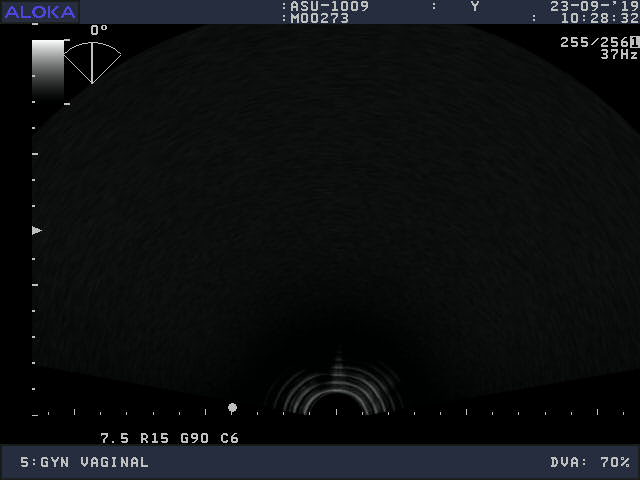

Volume Obstetric and Gynecology

Frequency Range: 9 – 3 MHz

Scan Angle: 163° FOV

Aloka ASU-1003 3D/4D Vaginal – ProSound for Volume Obstetric and Gynecology